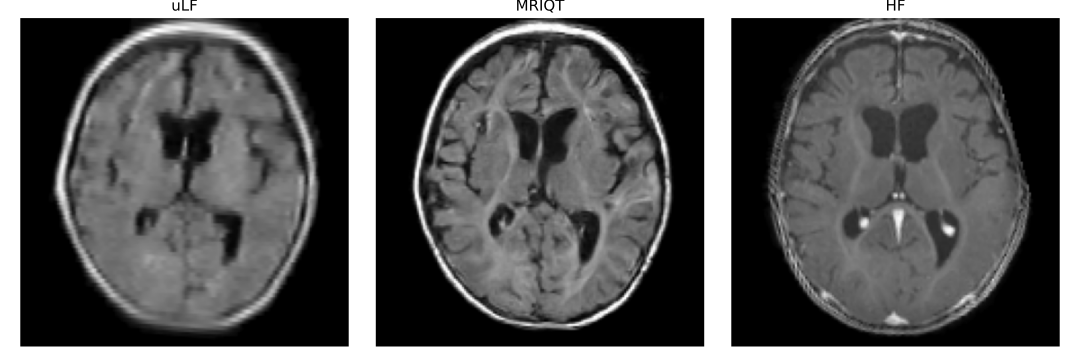

A sample of uLF, our MRIQT, and the HF for a selected case